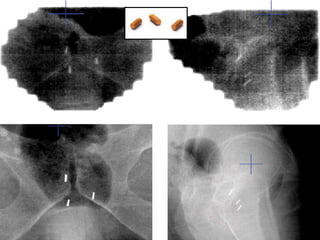

Prostate cancer is the second most common cancer globally, with varying incidence rates influenced by geography and lifestyle changes. In India, prostate cancer cases are rising due to urban migration and increased medical awareness, with current rates approaching those in Western countries. Treatment options vary by stage, including watchful waiting, surgery, radiation therapy, and hormonal treatment, each tailored to patient-specific factors.